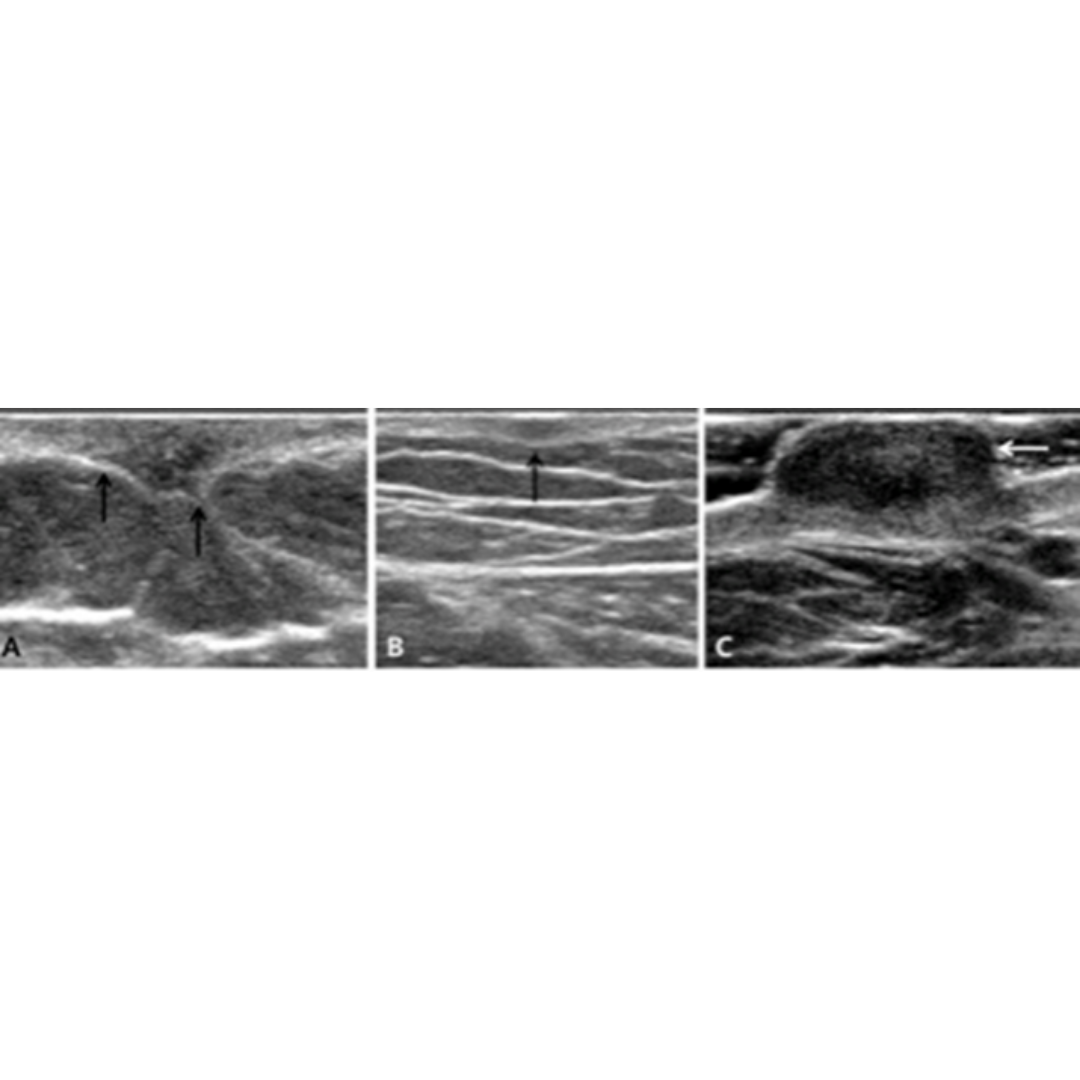

Lesión dermohipodérmica irregular, puede presentar espiculaciones, hipoecogénico respecto a la dermis, al Doppler no suelen vascularizar (Imagen 7)

Imagen 7: Diversos hallazgos ecográficos de dermatofibromas. (a) La ecografía de la pared abdominal en una mujer de 27 años muestra una lesión irregular que afecta la dermis y la capa de grasa subcutánea. Se observa espiculación de los márgenes. (b) La ecografía del muslo derecho en un hombre de 38 años muestra una lesión dérmica ovalada mal definida de 4 mm. (c) La ecografía del tobillo izquierdo en un hombre de 40 años muestra una lesión protuberante ubicada en la capa dérmica superficial.